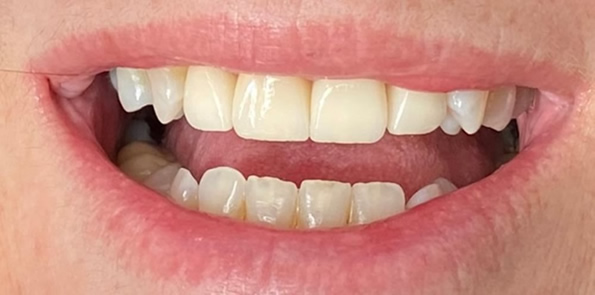

Próteses Fixa sobre dente

Tem a função de substituir um ou mais dentes perdidos ou destruídos. São próteses fixas na boca, presas sobre dentes e feitas de porcelana, podendo ser unitária ou múltipla (quando une três ou mais dentes para suprir uma ou mais ausência dentária).

Pode-se considerar também como prótese fixa, os laminados cerâmicos conhecidos como facetas e lentes de contato dental, mais indicados para o paciente que busca melhorar a estética em dentes anteriores.